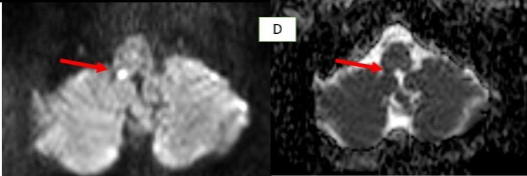

Methods: Two male patients presented with persistent hiccups, nausea, and vomiting. Imaging confirmed lateral medullary infarcts involving the area postrema. Etiological investigations included vascular imaging and thrombophilia workup.

Ischemic Area Postrema Syndrome (APS) is a rare neurological condition characterized by persistent nausea, vomiting, and hiccups resulting from an infarction in the area postrema, a highly vascularized, circumventricular structure in the dorsal medulla. Supplied by small perforating branches of the anterior spinal artery or vertebral artery, this chemoreceptor “vomiting center” lacks a typical blood–brain barrier, making it uniquely vulnerable to ischemic injury. Although ischemic stroke is an infrequent cause of APS, case reports—highlighting dorsal medullary infarcts confirmed on thin-slice diffusion-weighted MRI—demonstrate that small, localized ischemic events can disrupt the area’s function and induce classic APS symptoms.

| MRI Findings | Acute lateral medullary infarct (right area postrema), loss of normal flow void in right vertebral artery and PICA → intraluminal thrombus | Infarct in lateral medullary area, thrombus in right vertebral artery, T2 hyperintensities in bilateral cerebral hemispheres perpendicular to corpus callosum |

Early recognition of APS is crucial for timely diagnosis. In NMOSD, APS can precede MRI findings, warranting early immunotherapy. In contrast to stroke, APS in NMOSD is driven by autoimmune astrocytopathy, where anti-AQP4 IgG binds to astrocytic water channels in the area postrema, triggering complement activation and resulting in astrocyte loss, immunoglobulin/complement deposition, and inflammatory infiltrates. In a stroke, infarction leads to irreversible damage. Ischemic-stroke-induced Area Postrema Syndrome (APS) results from vascular occlusion—typically of perforating branches from the anterior spinal or vertebral arteries—leading to neuronal ischemia, necrosis, and microglial activation within the dorsal medulla, as demonstrated by diffusion-weighted MRI in case reports.